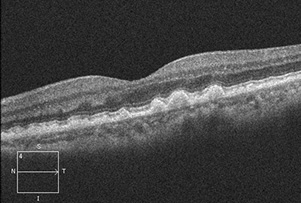

정상안

황반은 우리 눈에서 사물을 또렷하게 볼 수 있도록 도와주는 가장 중요한 부위입니다.

이 부위에 변화가 생기면 중심 시력이 떨어져 글씨가 흐려 보이거나 직선이 휘어져 보이는 증상이 나타나는데, 이를 황반변성이라고 합니다.